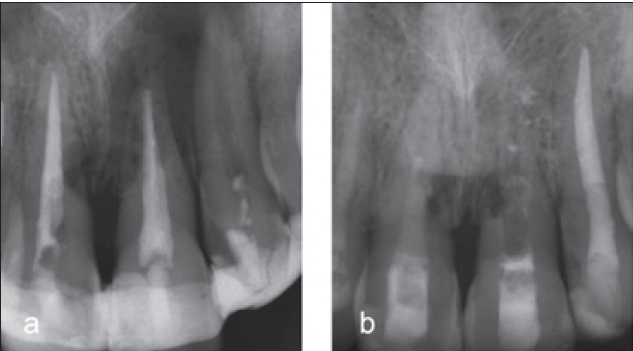

Regelmäßige Kontrolle

Falls das Ausmaß der Zerstörung sehr groß und keine Behandlung möglich ist, kann eine temporäre Erhaltung des Zahnes unter engmaschiger Kontrolle in Erwägung gezogen werden [32]. Dazu muss ein entzündungs- und symptomfreier Zustand vorliegen (Abb. 17). Im Zuge regelmäßiger klinischer und radiologischer Kontrollen sollte die Situation gemeinsam mit dem Patienten reevaluiert werden. Ästhetische und funktionelle Beeinträchtigungen wie Zahnverfärbungen, Infrapositionierung oder akute Entzündungen können letzten Endes den Anlass zur Entfernung des geschädigten Zahnes geben.